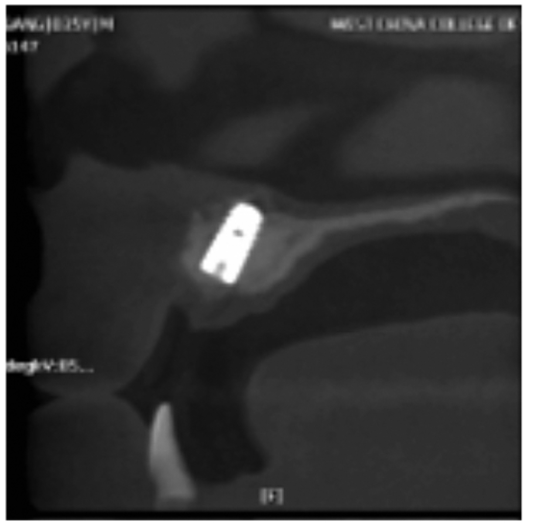

图8 术后CBCT片矢状位

显示种植体植入5个月后2期修复前的状况